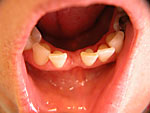

Die folgenden Patientenfälle sollen Ihnen einen Einblick in die Möglichkeiten der modernen Implantation geben.

Frontzahn-Implantation: